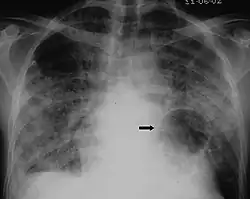

X-ray and CT of ground glass opacities and pneumothorax in pneumocystis pneumonia.[7]

Pneumothorax is a well-known complication of PCP.[8] Also, a condition similar to acute respiratory distress syndrome (ARDS) may occur in patients with severe Pneumocystis pneumonia, and such individuals may require intubation.[9]

The diagnosis can be confirmed by the characteristic appearance of the chest X-ray and an arterial oxygen level (PaO2) that is strikingly lower than would be expected from symptoms. Gallium 67 scans are also useful in the diagnosis. They are abnormal in about 90% of cases and are often positive before the chest X-ray becomes abnormal. Chest X-ray typically shows widespread pulmonary infiltrates. CT scan may show pulmonary cysts (not to be confused with the cyst-forms of the pathogen).